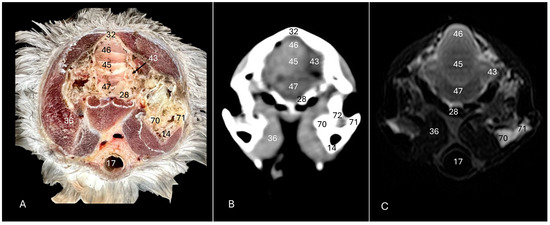

3. Result

3.1. Anatomical Sections

3.2. Computed Tomography (CT)

3.3. Magnetic Resonance Imaging (MRI)